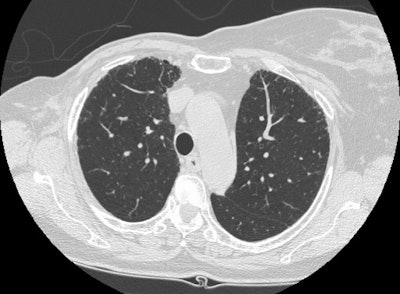

Earlier interstitial lung disease:

The case below is an example of interstitial lung disease at an earlier stage in a patient with a history of breast cancer (and a prior right mastectomy). There are patchy areas of fine subpleural "lace-like" intralobular interstitial thickening. Thickened interlobular septa are also seen, as is honeycombing- particularly in the posterior costophrenic sulci. The fibrosis associated with interstitial lung disease produces architectural distortion which is not seen in patients with lymphangetic metastases.